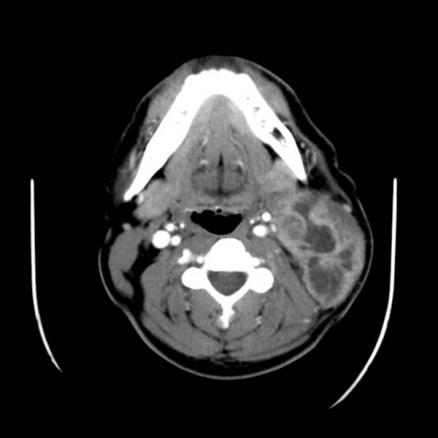

La Revue du Praticien - Hélène Leroy Masse latéro-cervicale gauche de 4 x 6 x 5 cm, à centre nécrotique.